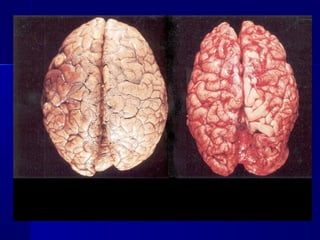

MMoorrpphhoollooggiiccaall cchhaannggeess iinn oorrggaannss aanndd ttiissssuueess

wwhhiicchh aarree ooccccuurrrreedd iinn ccoorrppsseess aatt aauuttooppssyy iinn

ccaasseess ooff cchhrroonniicc ccaarrddiioovvaassccuullaarr iinnssuuffffiicciieennccyy::

 ccyyaannoossiiss ooff sskkiinn..

 OOeeddeemmaa ooff ssuubbccuuttaanneeoouuss ffaattttyy ttiissssuuee

 aasscciittiiss ((hhyyddrrooppeerriittoonneeuumm)),, hhyyddrrootthhoorraaxx,,

hhyyddrrooppeerriiccaarrddiiuumm

 ""nnuuttmmeegg"" lliivveerr

 ""bbrroowwnn iinndduurraattiioonn"" ooff tthhee lluunnggss

 ccyyaannoottiicc iinndduurraattiioonn ooff kkiiddnneeyyss aanndd sspplleeeenn

MMoorrpphhoollooggiiccaall cchhaannggeess iinnoorrggaannss aanndd ttiissssuueess wwhhiicchh aarree ooccccuurrrreedd iinn ccoorrppsseess aatt aauuttooppssyy iinn ccaasseess ooff cchhrroonniicc ccaarrddiioovvaassccuullaarr iinnssuuffffiicciieennccyy::  ccyyaannoossiiss ooff sskkiinn..  OOeeddeemmaa ooff ssuubbccuuttaanneeoouuss ffaattttyy ttiissssuuee  aasscciittiiss ((hhyyddrrooppeerriittoonneeuumm)),, hhyyddrrootthhoorraaxx,, hhyyddrrooppeerriiccaarrddiiuumm  ""nnuuttmmeegg"" lliivveerr  ""bbrroowwnn iinndduurraattiioonn"" ooff tthhee lluunnggss  ccyyaannoottiicc iinndduurraattiioonn ooff kkiiddnneeyyss aanndd sspplleeeenn